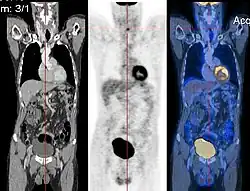

Image registration is a process that searches for the correct alignment of images.[21][22][23][24] In the simplest case, two images are aligned. Typically, one image is treated as the target image and the other is treated as a source image; the source image is transformed to match the target image. The optimization procedure updates the transformation of the source image based on a similarity value that evaluates the current quality of the alignment. This iterative procedure is repeated until a (local) optimum is found. An example is the registration of CT and PET images to combine structural and metabolic information (see figure).

The figure "Visualization of Medical Imaging" illustrates several types of visualization: 1. the display of cross-sections as gray scale images; 2. reformatted views of gray scale images (the sagittal view in this example has a different orientation than the original direction of the image acquisition; and 3. A 3D volume rendering of the same data. The nodular lesion is clearly visible in the different presentations and has been annotated with a white line.